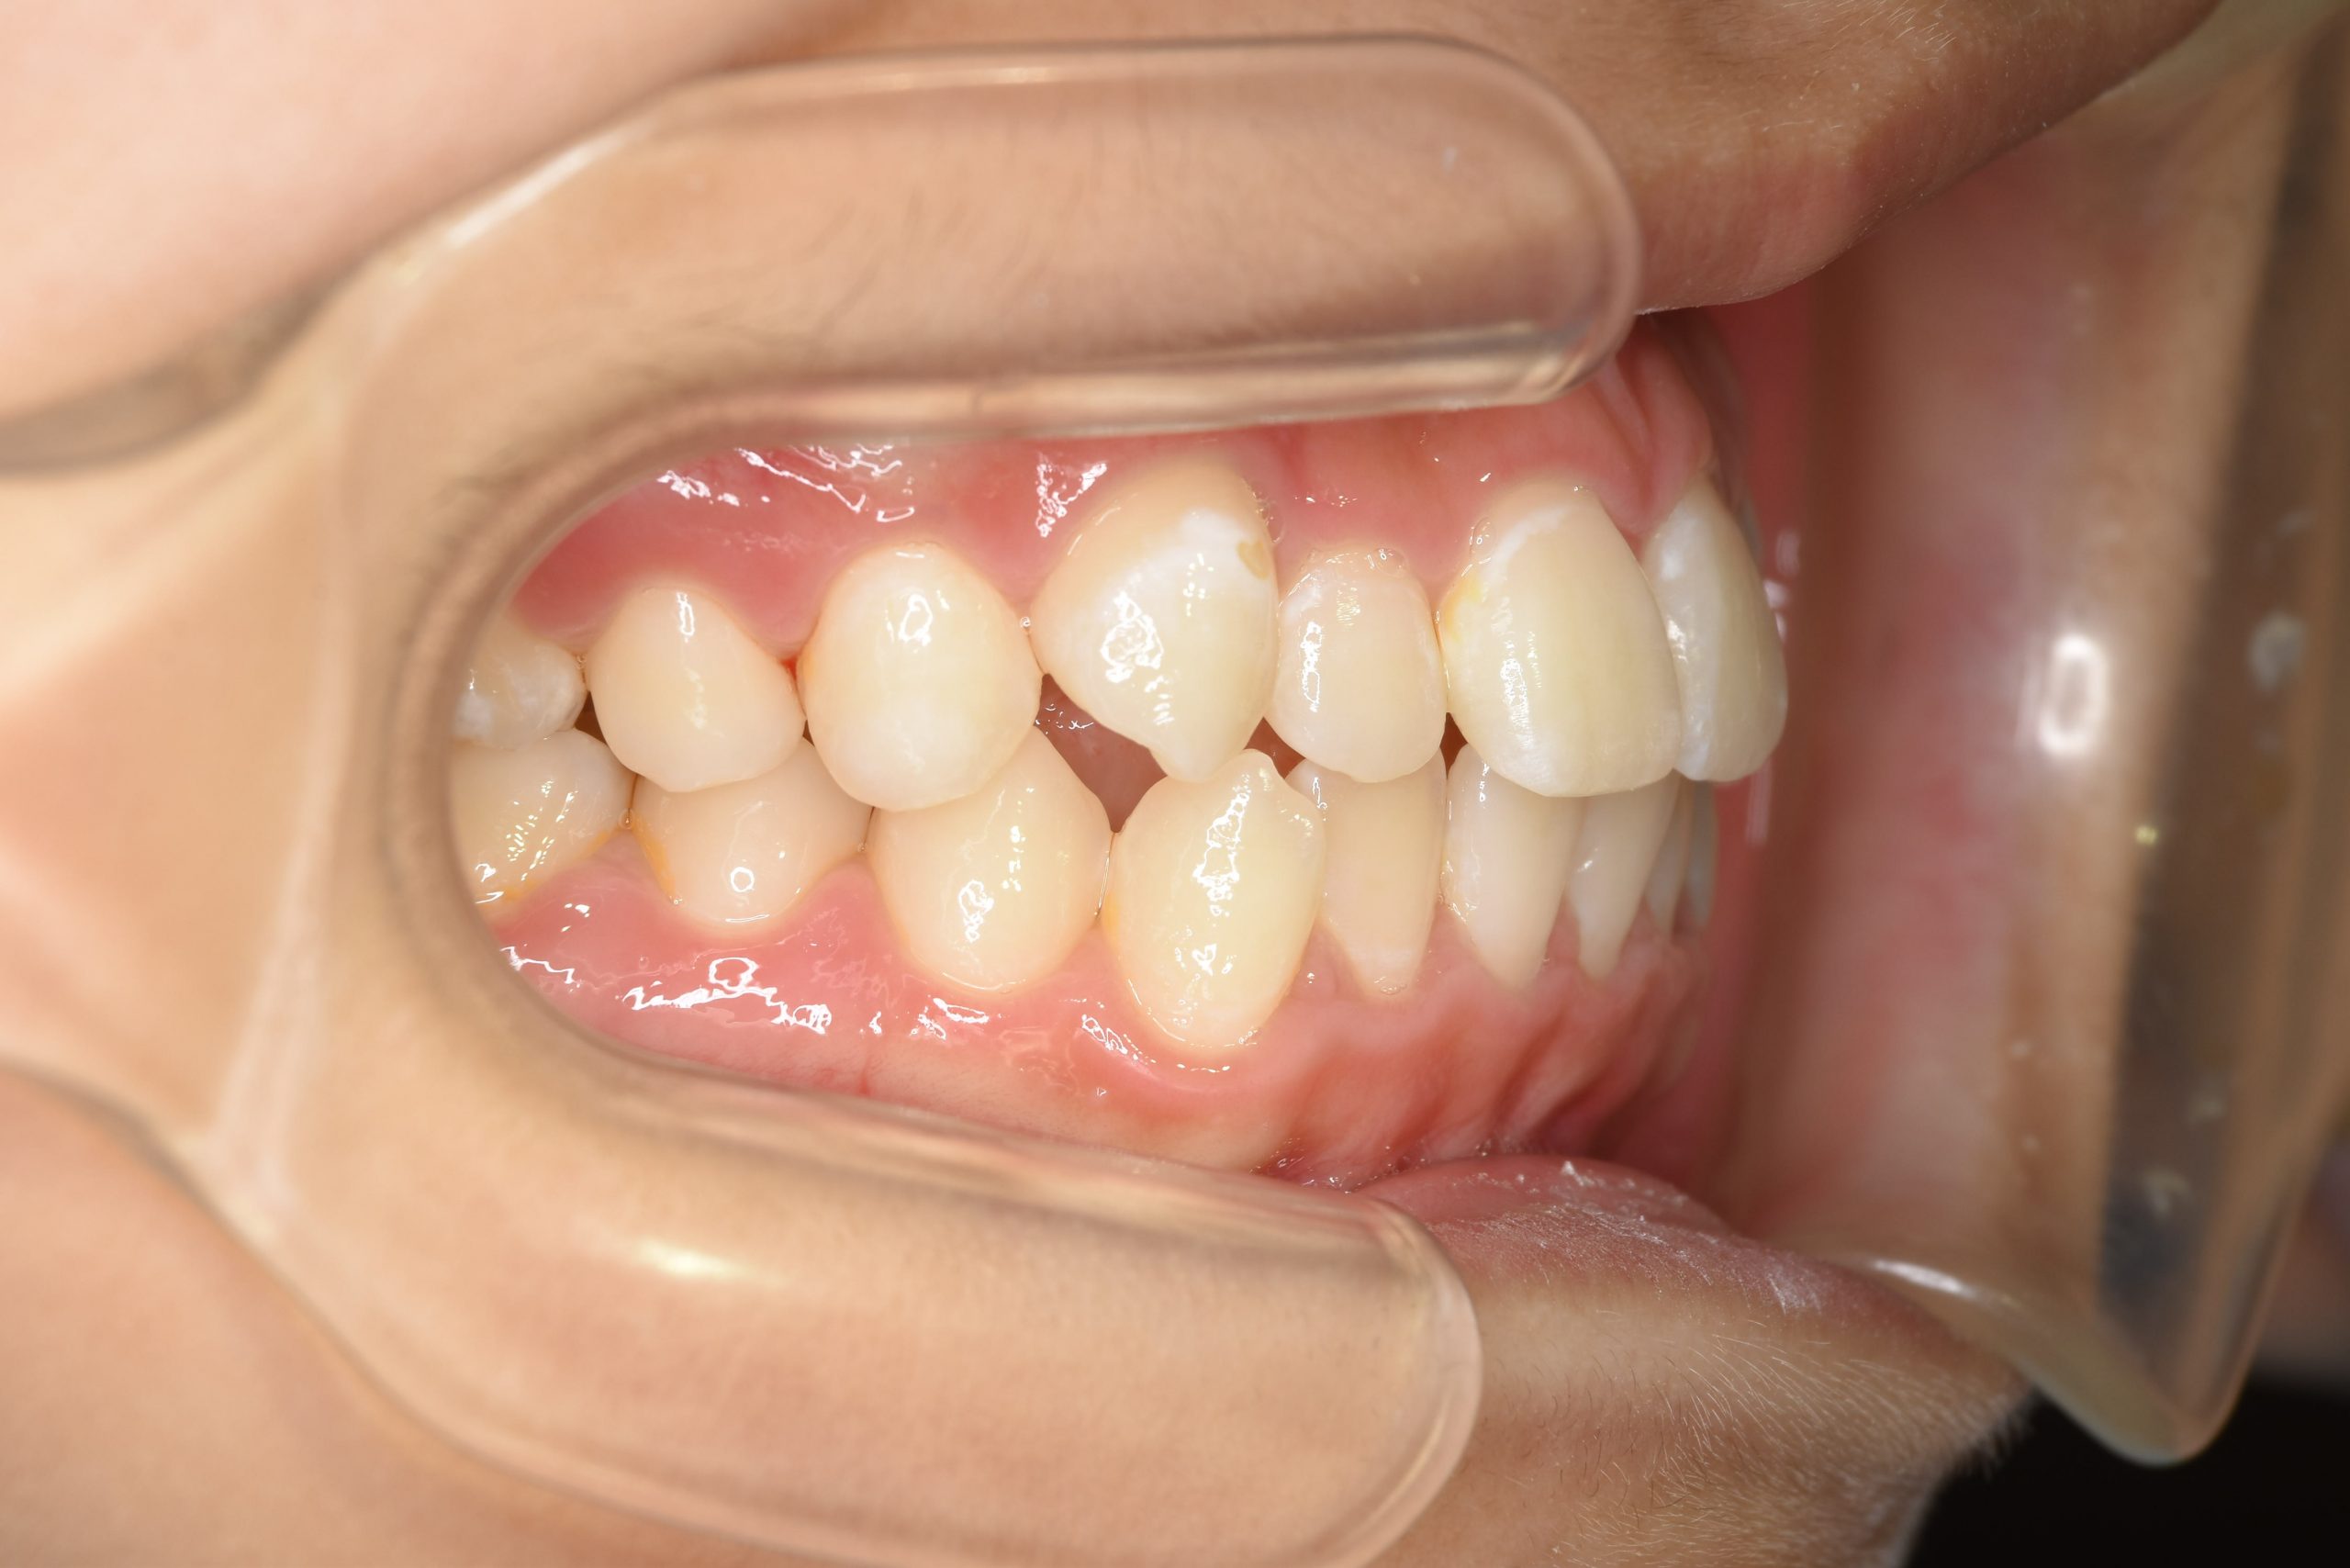

アフター

子どもの矯正治療|症例_169

施術内容 上顎急速拡大装置と下顎リンガルアーチを用いて上下顎骨を拡大した。

その後マウスピース型矯正装置で歯牙を配列し良好な咬合を獲得した。

治癒期間 3年5ヶ月間